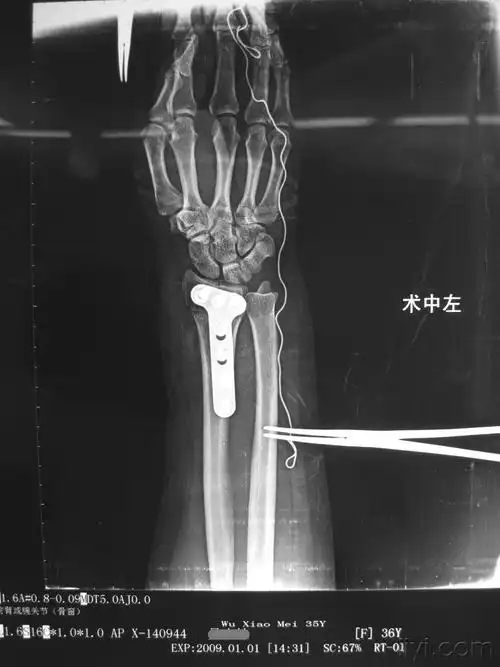

左陈旧性colles骨折一例